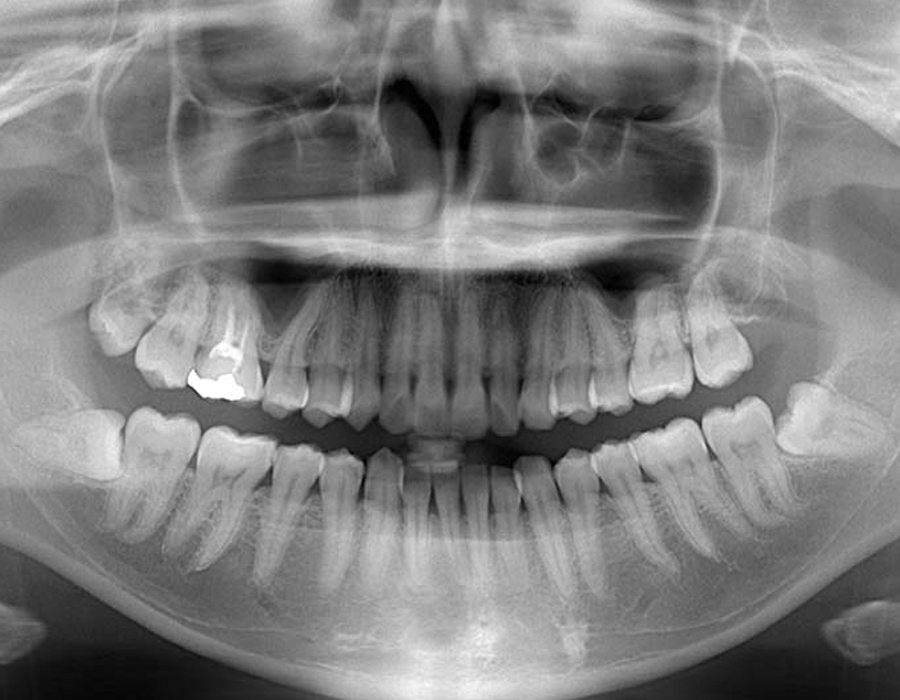

STEP 02検査&検診

短時間で安全に親知らずを抜歯するためには、事前の画像検査が欠かせません。CT撮影により、親知らずや顎の骨の状態を詳しく知ることができます。その上でお口の中を拝見します。現状と歯科医としての意見をお伝えし、患者様と話し合いながら、抜歯を行うのか、残して経過観察に留めるか決定します。

検査&検診